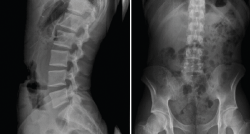

Proyecciones radiológicas

La más frecuentemente utilizadas son la proyección AP y L. Se debe procurar incluir al menos hasta T11 y el borde superior de las caderas (Figura 8).

Figura 8. Radiografía anteroposterior lateral y lumbar.

Las radiografías oblicuas no son necesarias de forma rutinaria, estando indicadas en pacientes con una elevada sospecha de presentar una espondilólisis (Figura 9).

Debe resaltarse que, en los casos de dolor lumbar atendidos en la mutuas de accidentes laborales, debido a las especiales características de la atención sanitaria que realizan y a la necesidad de determinar desde el primer momento la contingencia del proceso, es imprescindible realizar siempre al menos una radiografía anteroposterior (AP) y lateral (L) en bipedestación (o carga) de la columna lumbar.